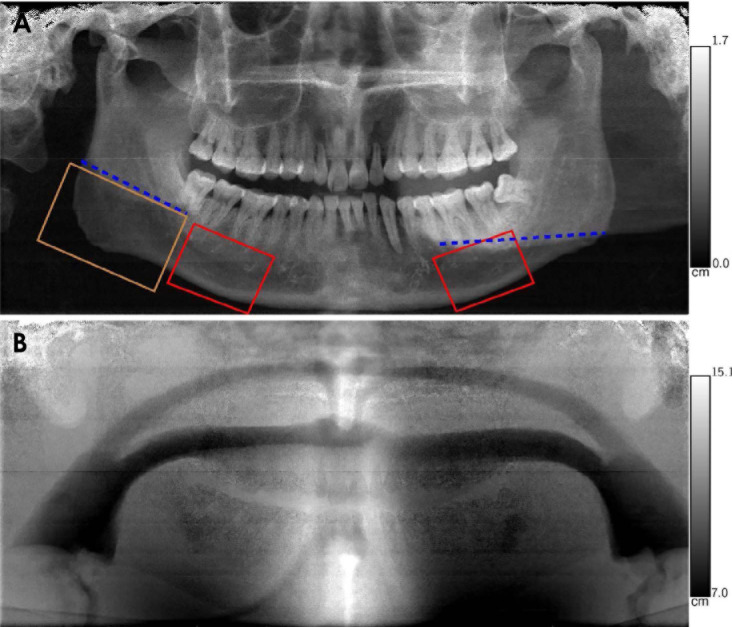

Purpose: This study demonstrated the feasibility of obtaining mandible bone mineral density (BMD) scores using spectral panoramic imaging.

Materials and methods: Areal BMD scores were measured from the body and angle of the mandible in 3 anthropomorphic head phantoms using a spectral panoramic system (Planmeca Promax Mid, Planmeca Oy, Helsinki, Finland) equipped with a DC-Vela detector (Varex Imaging Corporation, Salt Lake City, USA). These results were compared to synthetic panoramic images generated from dual-energy CT acquisitions. Reproducibility was evaluated by repeatedly scanning 1 phantom with minor patient positioning errors, and the linearity of the BMD scores was assessed using calcium inserts in a Gammex 472 phantom (Sun Nuclear, Melbourne, USA).

Results: The experimental and synthetic panoramic images appeared visually similar. The mean synthetic score was 0.640 g/cm2, and the anthropomorphic phantoms produced a root mean squared error of 0.0292 g/cm2 with a correlation coefficient of 0.969. Typical patient positioning errors did not substantially increase the error, which measured 0.0296 g/cm2 and 0.0474 g/cm2 for the left and right sides, respectively. Linearity tests using the Gammex phantom yielded a correlation coefficient of 0.998 for BMD scores ranging from 0.03 to 2.7 g/cm2.

Conclusion: The BMD data obtained from spectral panoramic imaging are consistent with both dual-energy CT and Gammex phantom measurements. Consequently, spectral panoramic imaging shows potential as a method for osteoporosis screening, leveraging the widespread use of panoramic imaging.